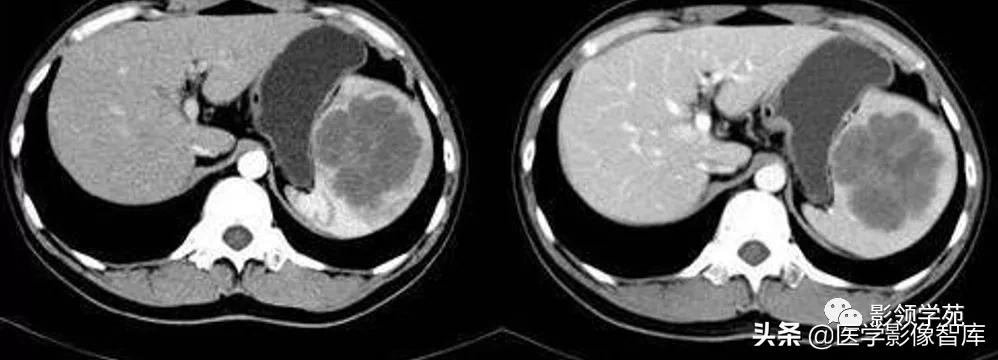

脾淋巴管瘤

脾淋巴管瘤(splenic lymphangioma)是一种少见良性淋巴管畸形。多为中青年患者。

病理学分为三种类型:①毛细血管性淋巴管瘤;②海绵性淋巴管瘤;③囊性淋巴管瘤。以囊性淋巴管瘤多见,病变累及多个脏器时称淋巴管瘤病。

【CT表现】

CT平扫:脾脏增大,脾实质内见单发或多发的低密度病灶,边界清晰,病灶内见粗大分隔。

增强扫描:病灶边缘及分隔有轻度强化,中央无明显强化,囊壁显示清晰。

鉴别诊断:脾淋巴管瘤的CT表现类似囊肿,其CT值比囊肿要高,且有粗间隔,增强扫描见边缘和间隔强化,并见囊壁显示,而脾囊肿密度均匀,增强无囊壁显示。